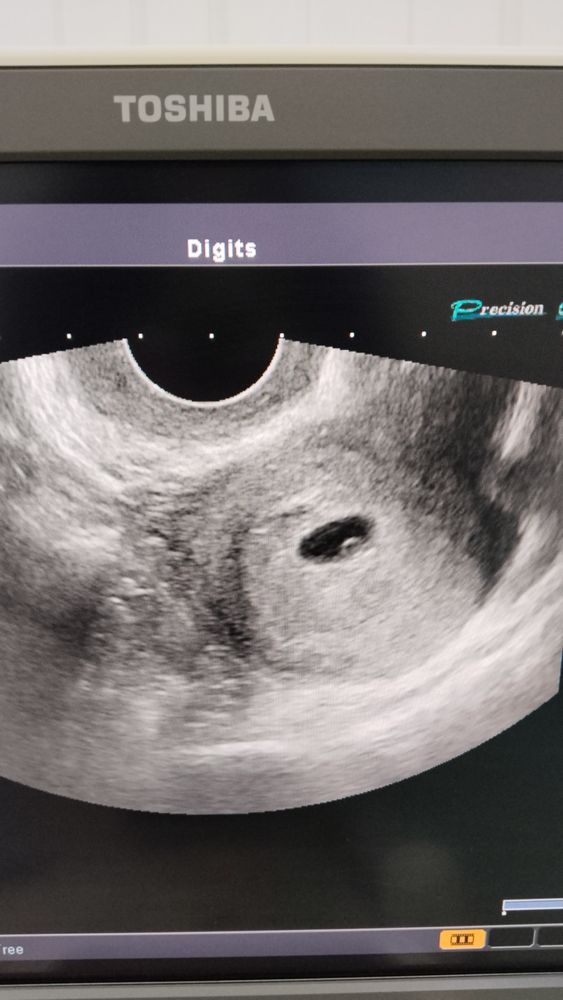

- ПЯ 12мм, ЖМ 3мм и сейчас посмотрим сердечко! Вот оно! Мерцает,

Сердцебиение + !!!

Делюсь с вами, фото нашего долгожданного чуда !))) Думаю каждая согласиться это прелесть , на которую можно любоваться вечно)))